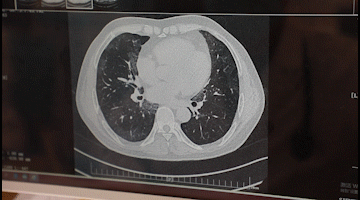

李先生入院后,胸科醫(yī)院吳昌歸院長(zhǎng)、朱運(yùn)奎副院長(zhǎng)組織科室進(jìn)行了深入討論,為其做了詳細(xì)檢查。醫(yī)生先做了導(dǎo)航下氣管鏡冰凍活檢,但病理未獲明確診斷。根據(jù)胸部CT特征、病變過(guò)程治療的反應(yīng),醫(yī)生懷疑是罕見的肺泡蛋白沉積癥。再經(jīng)肺泡灌洗液分析、PAS染色及診斷性分段灌洗后復(fù)查,證明醫(yī)生診斷正確。李先生確診為“肺泡蛋白沉積癥(繼發(fā)性)、肺炎、1型呼吸衰竭,并伴有慢性乙肝、高血脂癥等。

經(jīng)過(guò)4次的治療,李先生沉著于肺泡內(nèi)蛋白樣物質(zhì)漸漸消失,灌洗液為透明色。復(fù)查胸部CT肺部病變明顯吸收。經(jīng)再次灌洗治療后病變完全吸收,恢復(fù)健康。